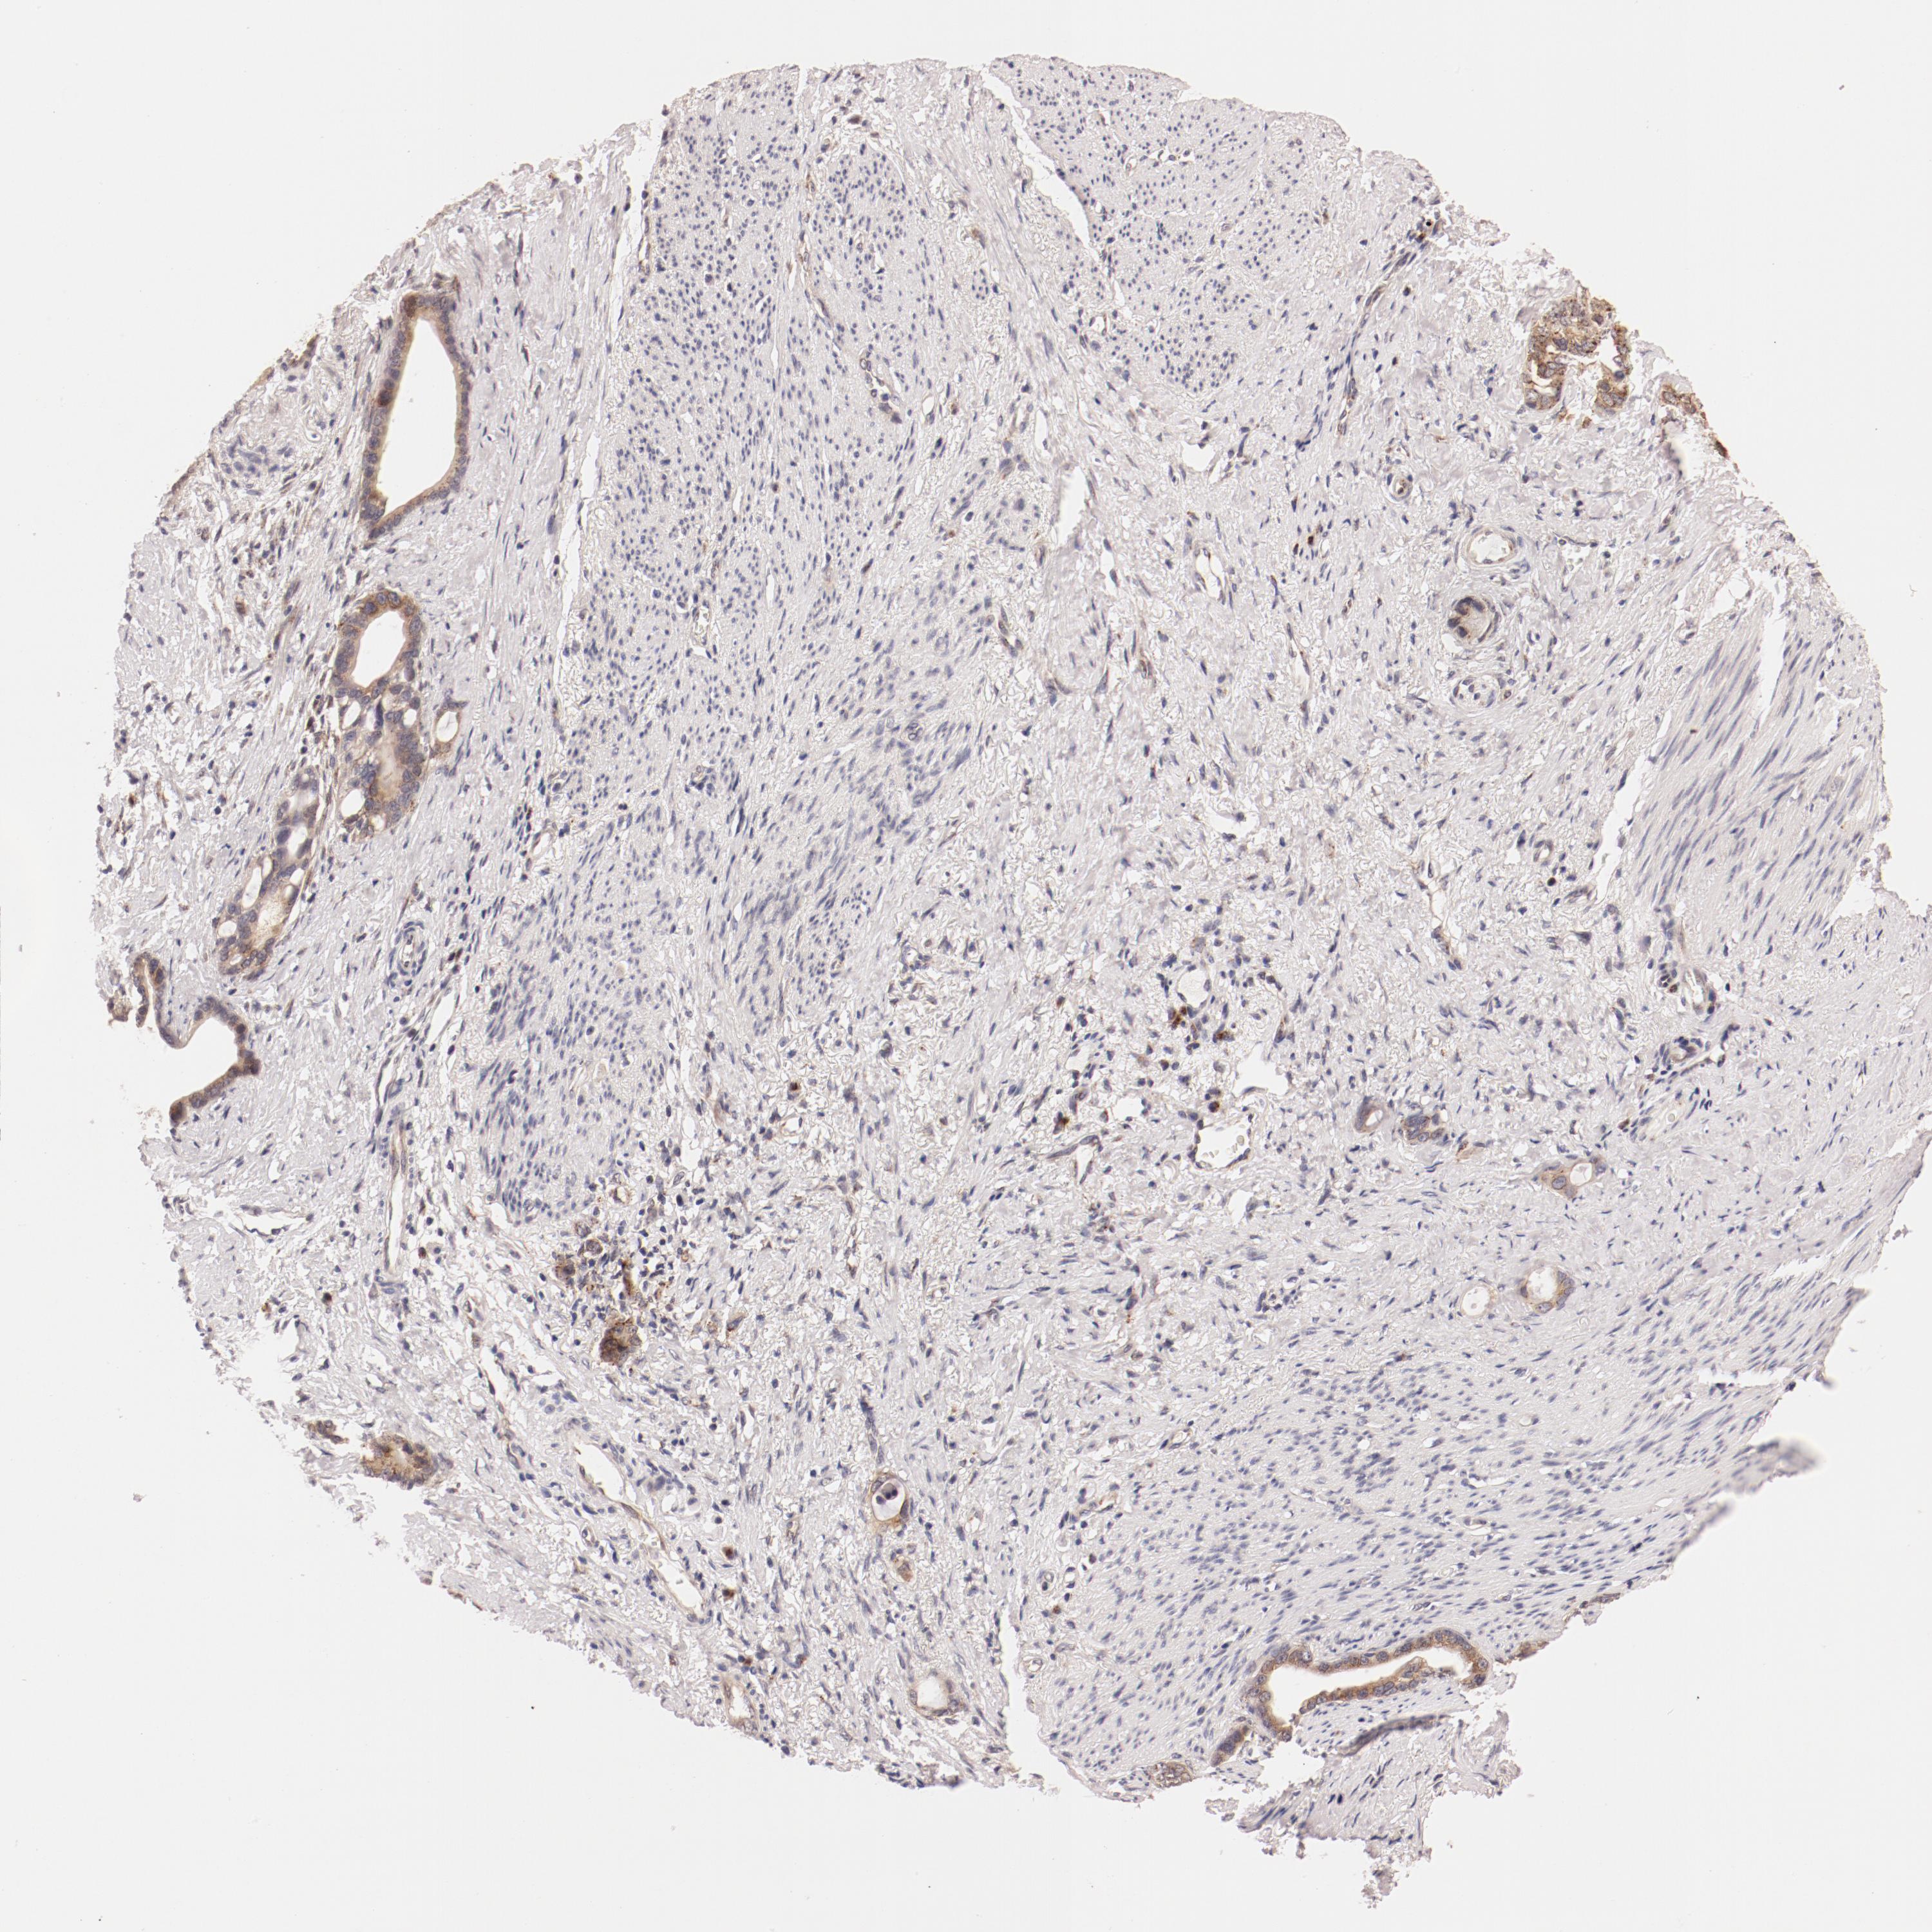

STOMACH CANCER - Protein expressioni

A mouse-over function shows sample information and annotation data. Click on an image to view it in a full screen mode. Samples can be filtered based on level of antibody staining by selecting one or several of the following categories: high, medium, low and not detected. The assay and annotation is described here.

Note that samples used for immunohistochemistry by the Human Protein Atlas do not correspond to samples in the TCGA dataset.

Antibody stainingi

Antibody staining in the annotated cell types in the current human tissue is reported as not detected, low, medium, or high, based on conventional immunohistochemistry profiling in selected tissues. This score is based on the combination of the staining intensity and fraction of stained cells.

Each image is clickable and will lead to virtual microscopy that enables deeper exploration of all samples and also displays staining intensity scores, fraction scores and subcellular localization as well as patient and tissue information for each sample.

Antibody HPA003403

Staining

High

Medium

Low

Not detected

Intensity

Strong

Moderate

Weak

Negative

Quantity

>75%

75%-25%

<25%

None

Location

Nuclear

Cytoplasmic/membranous

Cytoplasmic/membranous,nuclear

Adenocarcinoma, NOS

Adenocarcinoma, High grade